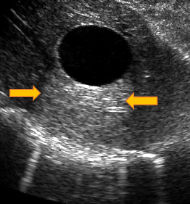

25

énorme structure anéchogène => bassinet extrêmement dilaté de liquide => hydronéphrose (obstruction urétérale)